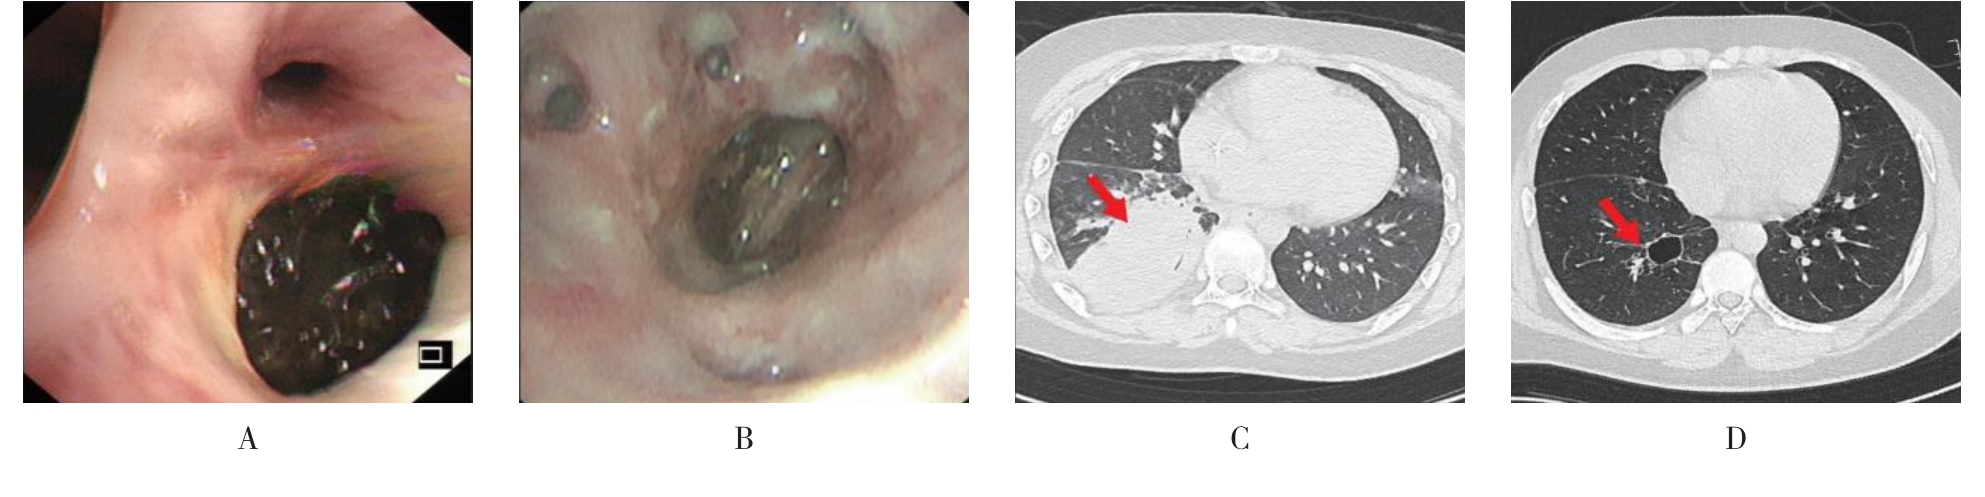

• 侵袭性肺真菌病的支气管镜表现及介入治疗效果

2025, 31(9):81-90. DOI: 10.12235/E20250317

摘要 (112) HTML (56) PDF 6.06 M (77) 评论 (0) 收藏

摘要:目的 探讨侵袭性肺真菌病(IPFD)的支气管镜表现,并评估介入治疗的安全性和疗效。方法 回顾性分析2018年5月12日-2025年5月12日于该院行支气管镜检查的35例IPFD患者的临床资料,观察IPFD的支气管镜表现及介入治疗效果。结果 共收集35例患者临床资料。其中,男22例,女13例,患者年龄(53±14)岁。基础疾病包括:血液系统恶性肿瘤10例,长期应用糖皮质激素者5例,2型糖尿病者4例,肺部恶性肿瘤2例,器官移植1例。胸部CT显示:肺部病变累及单肺叶者19例,累及多肺叶者16例。支气管镜下表现主要为:黏膜充血水肿29例(82.9%)、坏死物堵塞管腔22例(62.9%)、大量黏稠脓性分泌物17例(48.6%)、支气管部分狭窄或闭塞16例(45.7%)、黏膜坏死9例(25.7%)、黏膜出血5例(14.3%)、真菌球3例(8.6%)。其中,32例(91.4%)接受全身性抗真菌治疗,17例(48.6%)接受支气管镜局部两性霉素B灌注治疗,10例(28.6%)采用活检钳钳除病灶,6例(17.1%)采用冷冻探头冻取病灶,4例(11.4%)接受氩气刀治疗。28例(80.0%)临床症状明显改善,肺部影像学病灶缩小或消退;4例(11.4%)病灶稳定;3例(8.6%)未完成治疗。结论 IPFD多见于免疫抑制宿主,支气管镜常表现为:坏死物堵塞管腔、伴脓性分泌物、支气管管腔狭窄和局部黏膜充血水肿或坏死。全身抗真菌药物联合支气管镜下介入治疗,安全性高,且疗效好。